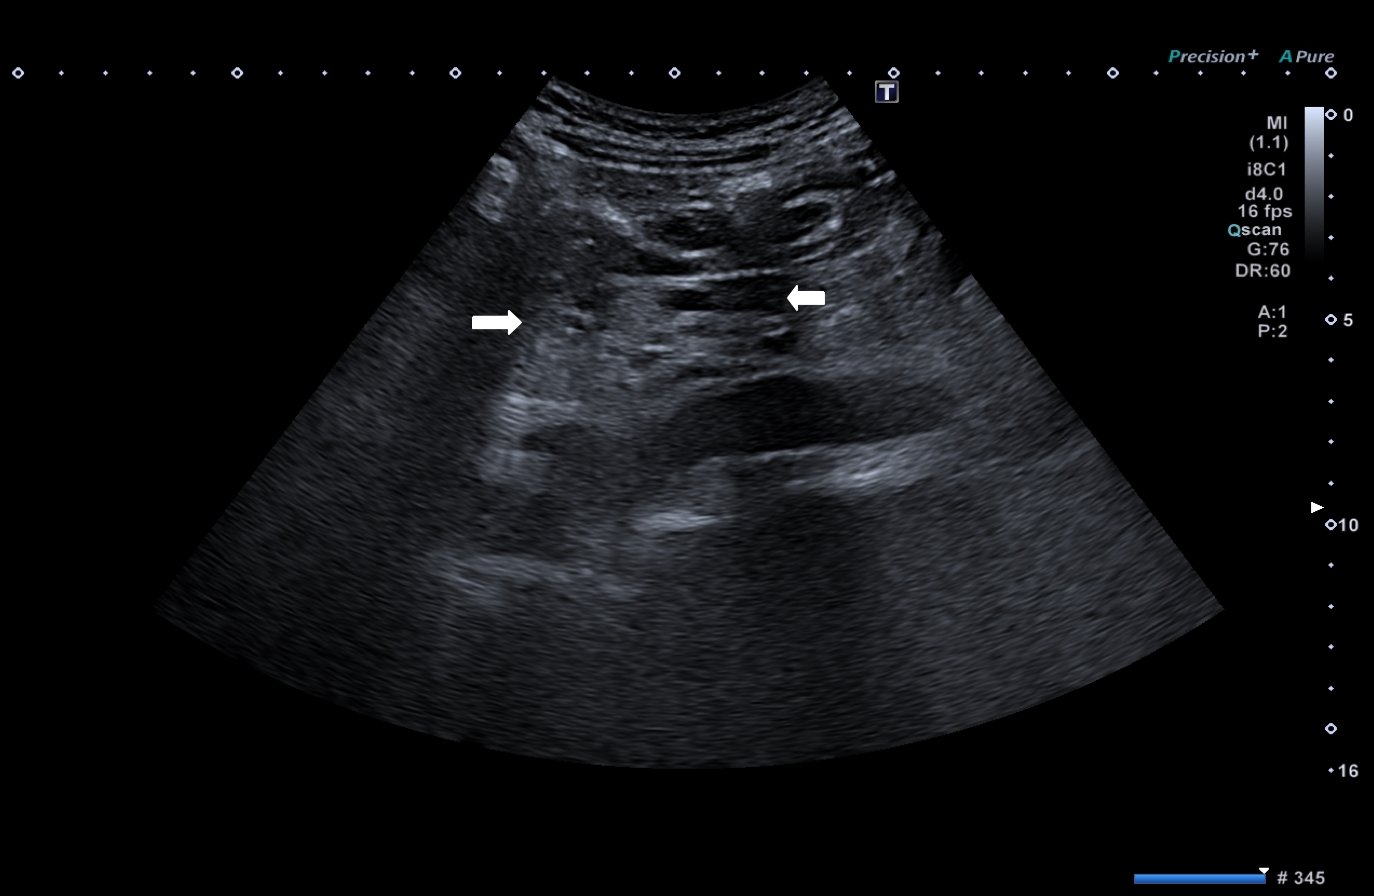

Bowel ultrasound findings in SARS-CoV-2 Pneumonia patients with gastrointestinal symptoms [Jan 2021]